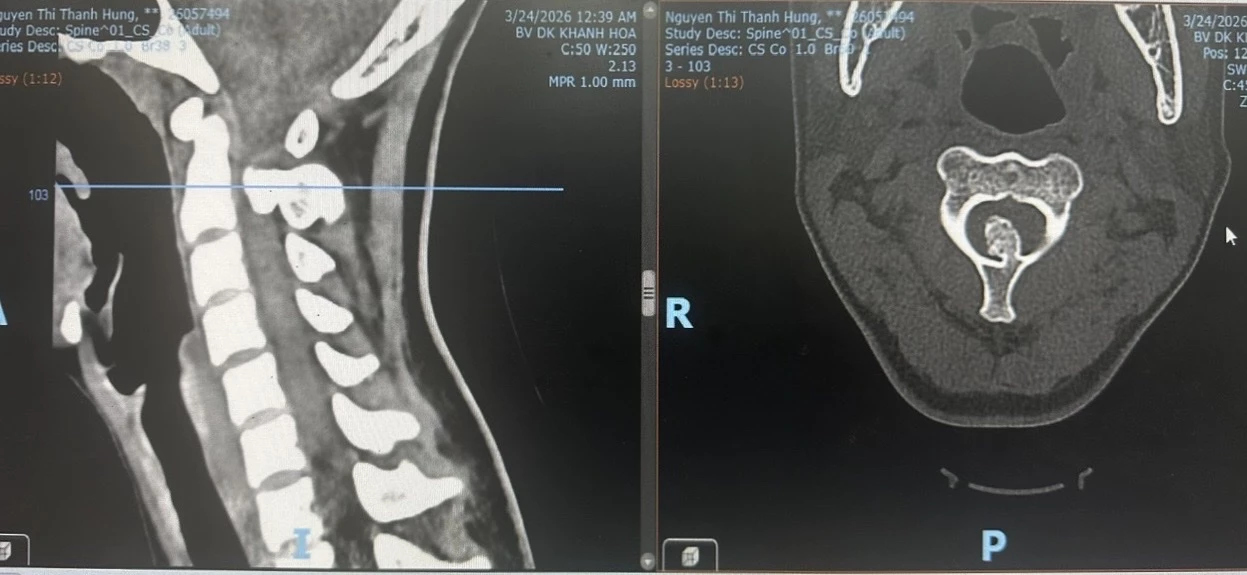

Theo đó, bệnh nhân H. có tiền sử bị tê tứ chi thoáng qua khi thực hiện động tác xoay cổ. Tối 23-3, trong lúc chơi đùa với bạn, bệnh nhân bị giữ đầu và thực hiện động tác xoay cổ, sau đó đột ngột đau cổ dữ dội, tê và yếu dần tay chân, không thể vận động bình thường nên được đưa vào bệnh viện cấp cứu. Qua thăm khám, bác sĩ ghi nhận bệnh nhân đau cổ nhiều, tê tứ chi, liệt vận động tứ chi không hoàn toàn. Kết quả từ các kỹ thuật cận lâm sàng cho thấy, tủy cổ tại đốt sống cổ thứ 2 bị chèn ép rất nặng do khối u xương xâm lấn vào ống sống.

Hình chụp MRI thấy rõ khối u xương cổ chèn ép tủy sống.